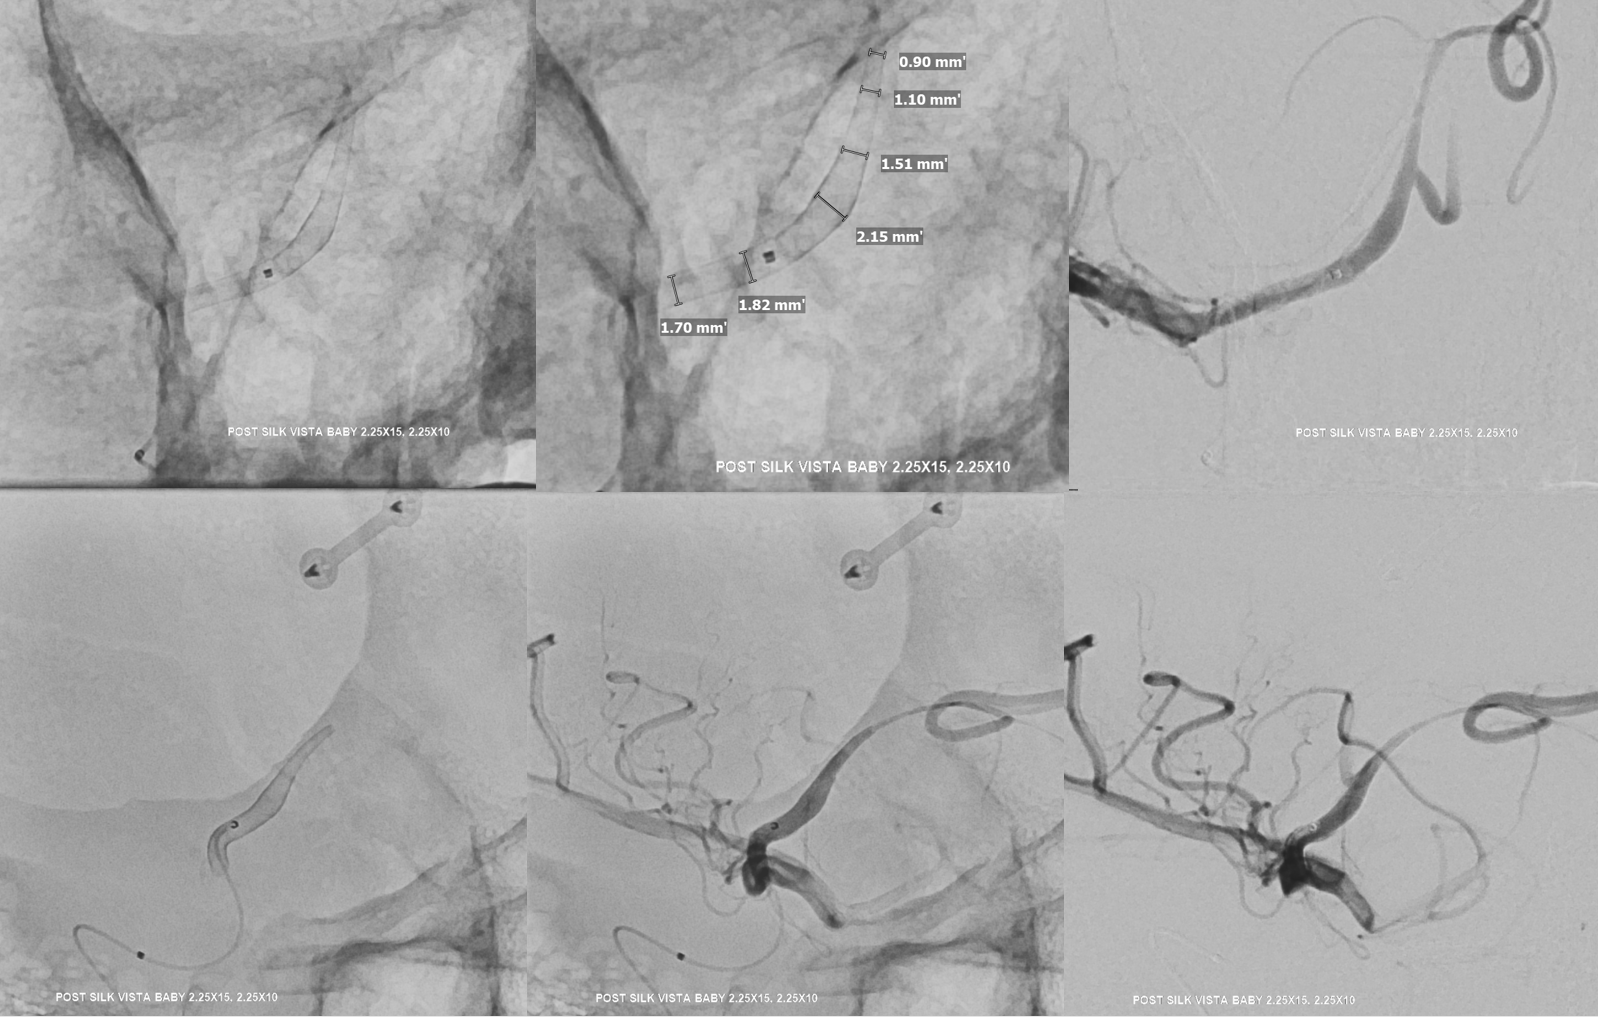

The first SVB is deployed. However, there is a concern. What is it? Look at the measurements of the SVB and the landing zones

The answer is possible endoleak. The distal landing zone may be too short for a nitinol device. The diameter of the proximal SVB is smaller than the expected diameter of the A2 target. Its a critical point. If this is missed, the treatment may fail

The answer is to either balloon it or put in another device. We put in another SBV, now extending it into one of the A2 branches. Yes, one can argue that with working bypass you can just close the A1-A2 junction. Sure. But we did not know this before. And we can always do that later by coiling inside the SVB. Here, we keep options open.

Post SVB 2

Look at the difference in measurements after SBV 2 (top row) and SBV 1 (bottom row). Arrows point to location of the SVB 1 distal landing zone

Now to the left side

Two Pipe Shields are placed. This is how we work. This big one is not a job for one and done

Post. Bilateral injections. The right ACA is supplied retrogradely via the ACA-ACA bypass. The MOST important finding here is that there is no longer flow across the ACOM. This is what flow modification is. Changing dynamics to impact aneurysm.